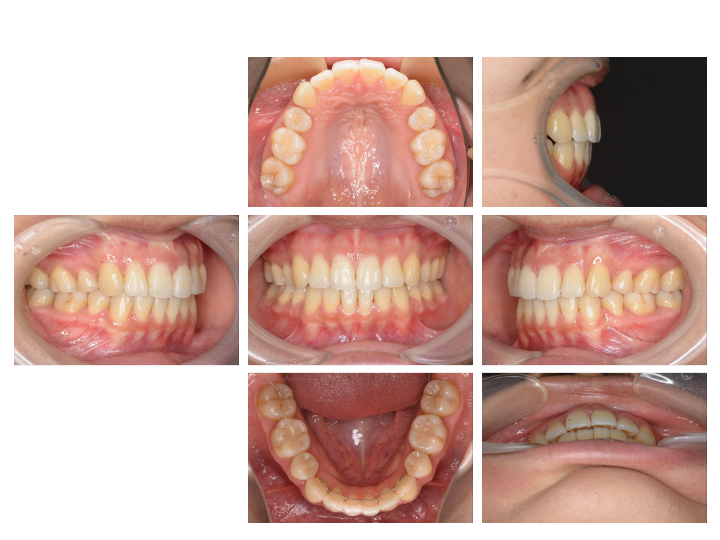

ですが、当院の「骨格にフォーカスした矯正」ならほとんどが小児矯正(およそ2年)で終わります。

1.治療期間が短く7割が幼少期で完治

せっかく並べた歯が後戻りしないよう骨格から整え、短い期間で治療が終えられるようにサポートいたします。